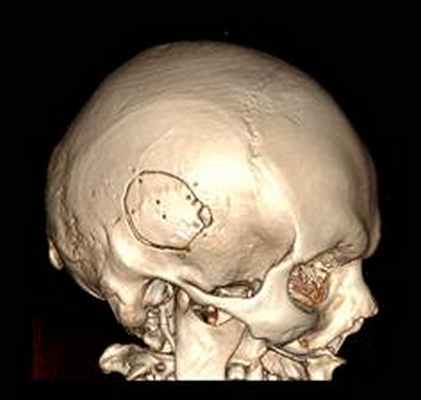

КТ головного мозга с контрастным усилением (24.03.2015): объемное кистозно-солидное образование правой теменно-височно-лобной области. Дислокационный синдром.

22.10.2015 была выполнена операция: микрохирургическое удаление опухоли правой височной доли под интраоперационными навигационным контролем и с интраоперационной фотодинамической терапией.

КТ головного мозга (23.10.2015): не выявило признаков кровоизлияния или каких-либо других хирургических осложнений в области оперативного вмешательства.